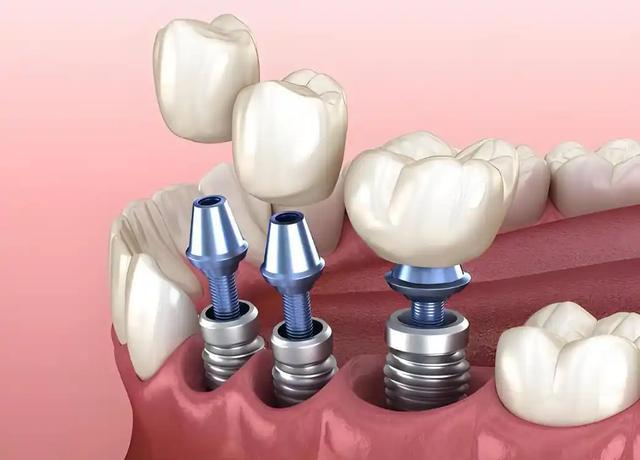

种植牙简单来说,就是将医用钛合金种植体通过手术植入牙槽骨内,替代天然牙根,再在上面安装牙冠,从而恢复牙齿的咀嚼和美观功能,规范操作下成功率可达95%以上。

因此被业界称为人类的第三副牙齿。但它本质上是一项有创外科手术,涉及骨结合、口腔微生物环境等多个复杂环节,其中哪一步最容易出现问题,引发风险呢?